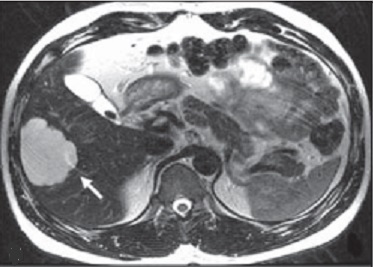

Image IRM de adenome du foie : Lesion est

hypersignal T1 et T2 par le caracteristique de la presence

de graisseux intracellulaire pres de 75% des cas .

Rehaussement important sur des zones non necrotique et non

hemorrhagique .

Áspect radiologique IRM

en T1 de adenome du foie droit : Image hypersignal

de multiple de adenome du foie gauche |

|

Même cas en T2 fat sat :

Image IRM T2 du foie en coupe axiale |

Image du foie en T2 . : Image

hypersignal des adenome du foie droit |

Image radiologique

hypersignal d'une

adenome du foie . Image IRM ponderee en T2 |